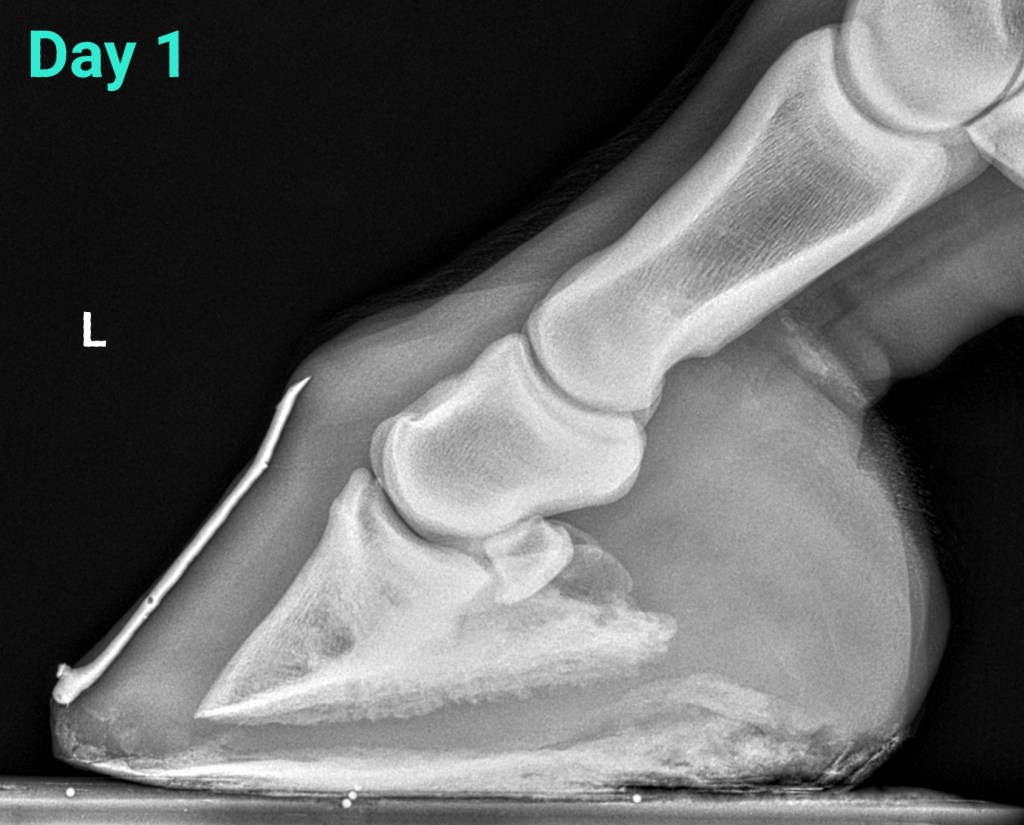

Acute, mild laminitis episode

28 year old Haflinger gelding – overweight. He was placed in NANRIC Ultimates. Caloric intake was reduced and exercise was restricted.

2 months later the horse is sound, he has doubled his sole depth, and improved alignment. I gradually reduced the size of heel elevation and finally removed the Ultimates.